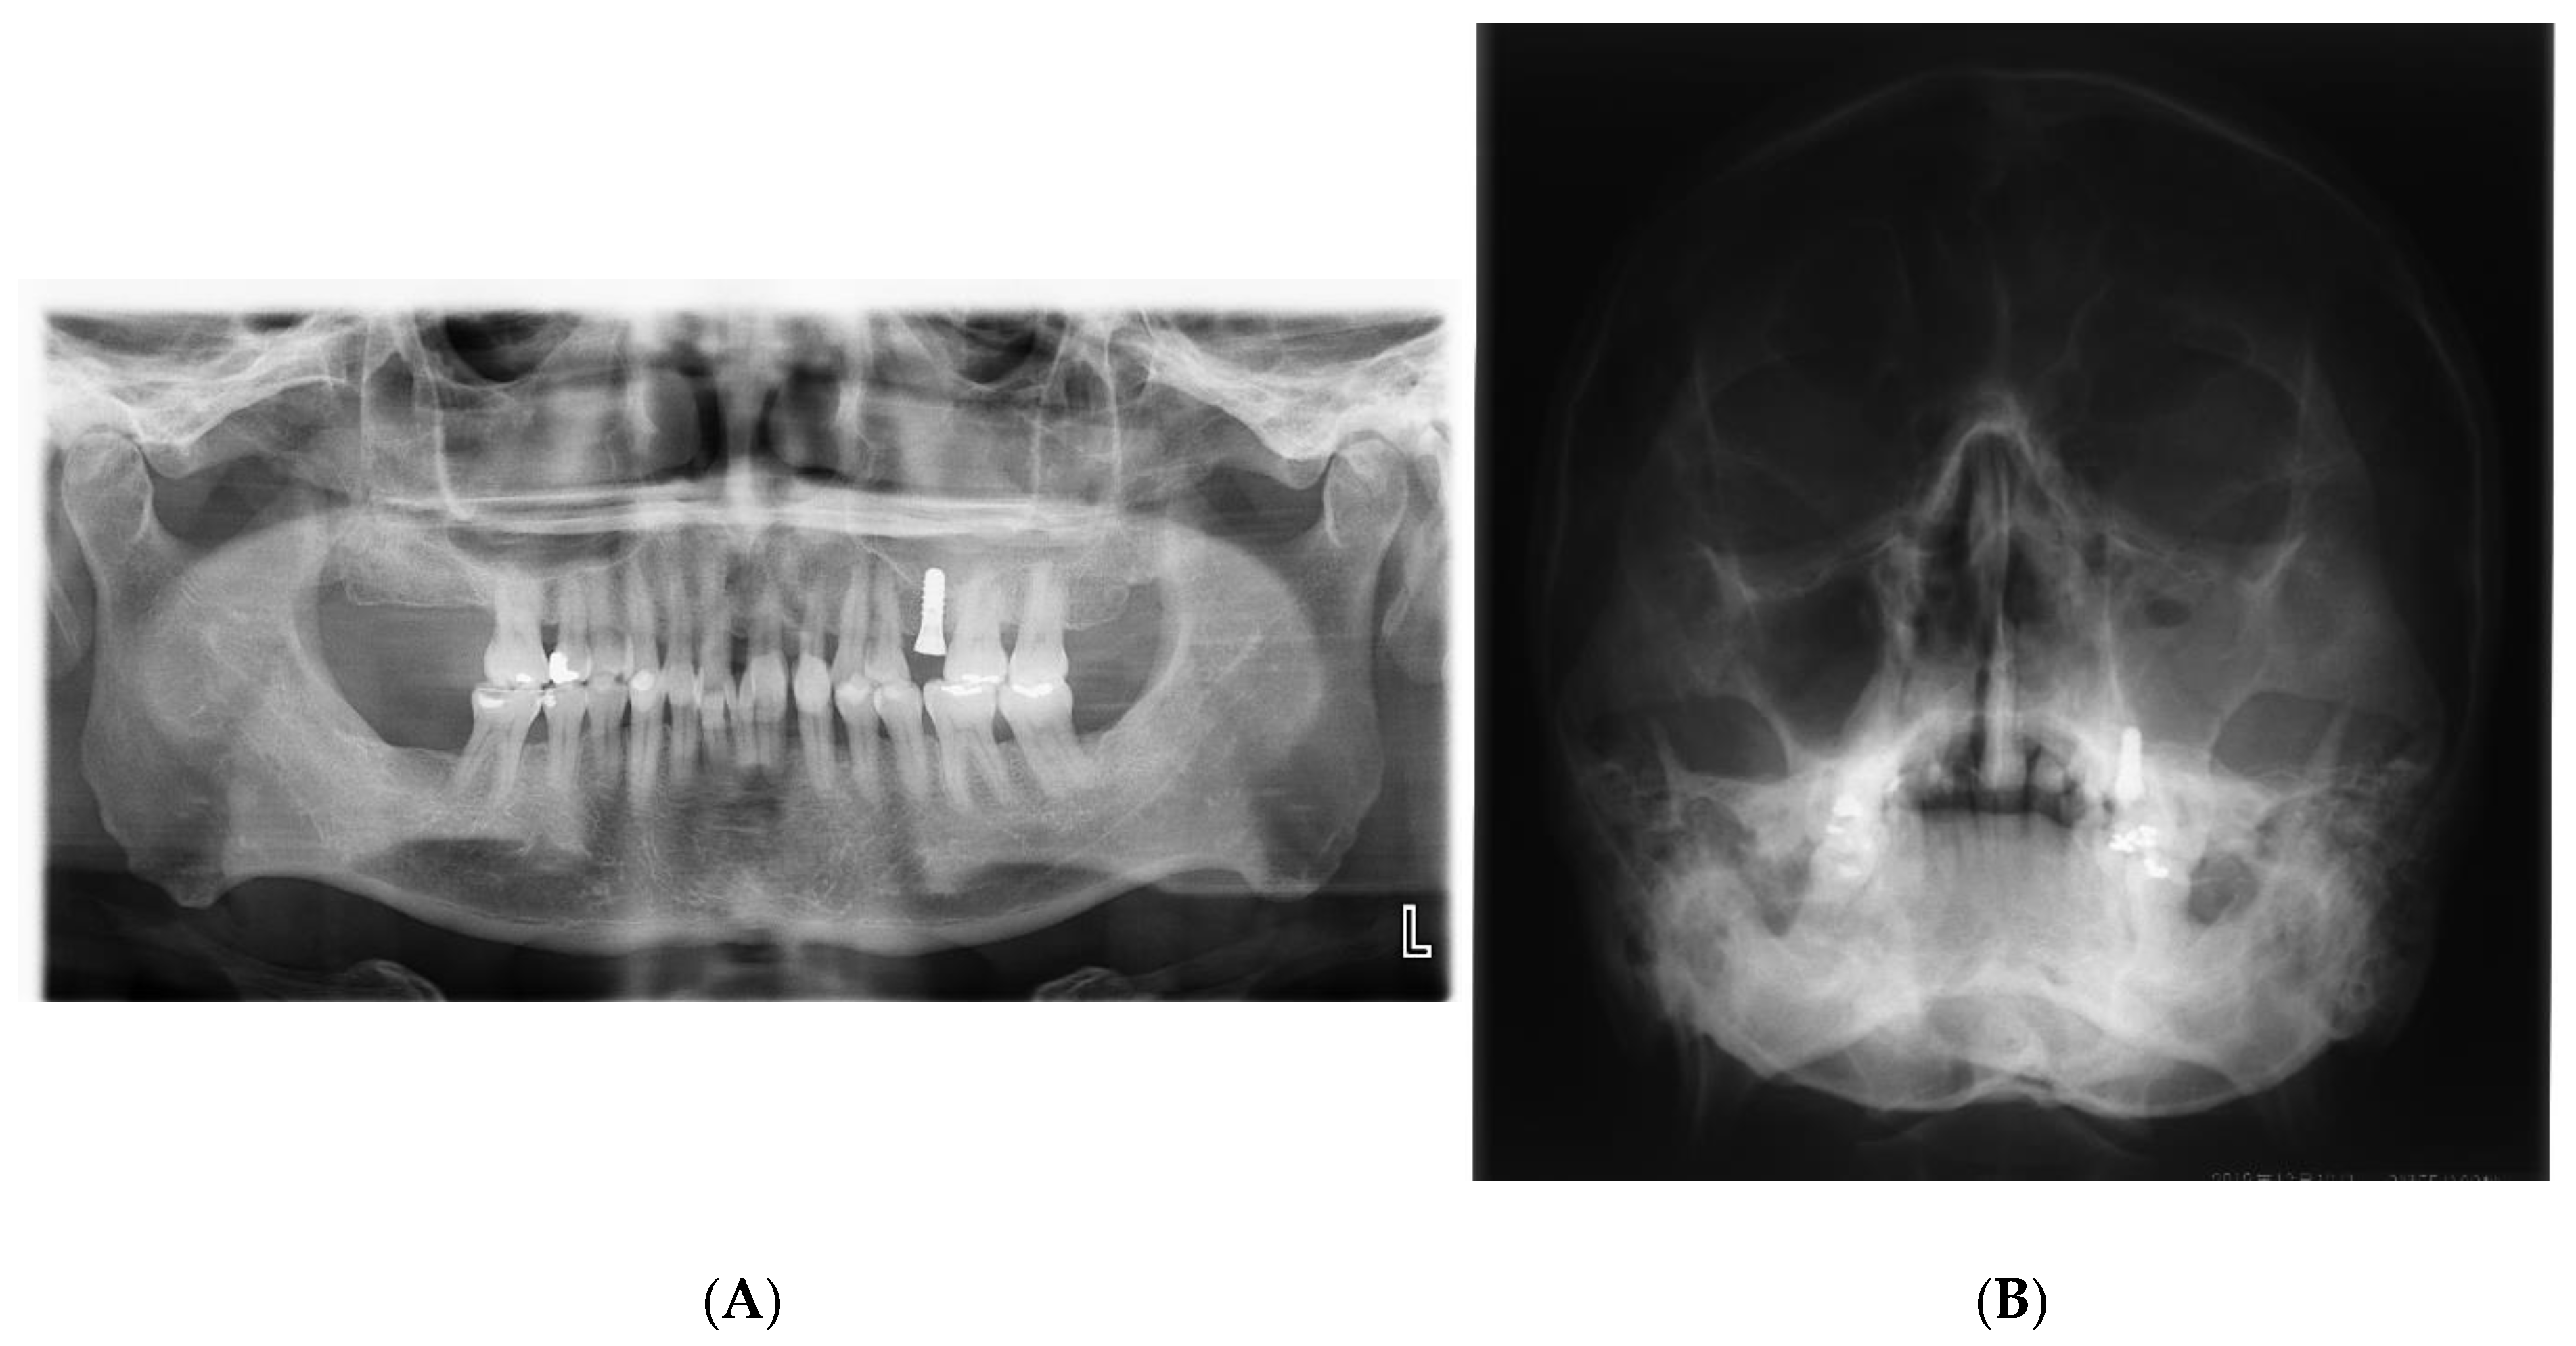

2. Identification of the Possible Causal and Risk Factors for Maxillary Sinusitis after Implant Surgery with or without Sinus Augmentation

2.2. Dental Causes such as Poor Oral Hygiene, Persistent/Recurrent Periodontitis, and Peri-Implantitis

2.3. Alterations of the Anatomical Structure That Can Facilitate the Impairment of the Maxillary Sinus Drainage Pathway